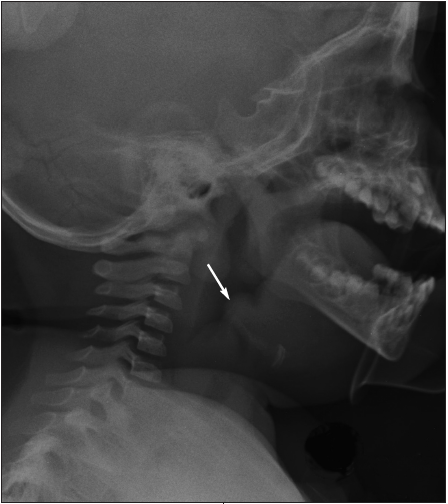

Anteroposterior and lateral neck radiographs demonstrated an enlarged epiglottis with effacement of the vallecula and thickening of the aryepiglottic folds and pharyngeal edema. Laryngoscopy demonstrated a severely edematous and erythematous epiglottis. The true vocal cords were normal. Aerobic and anaerobic culture specimens from the surface of the epiglottis were obtained.